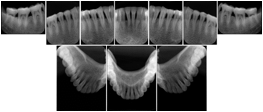

2. A patient requests cosmetic surgery to enhance their facial appearance. The case requires consultation between an orthodontist in New York and an oral surgeon in California. The cephalometric series of 2D projections constructed from the volumetric CT data that is used for the discussion is arranged by a Structured Display for transfer between the two practitioners.

Cephalometric Series Structured Display

Figure OO-2. Cephalometric Series Structured Display